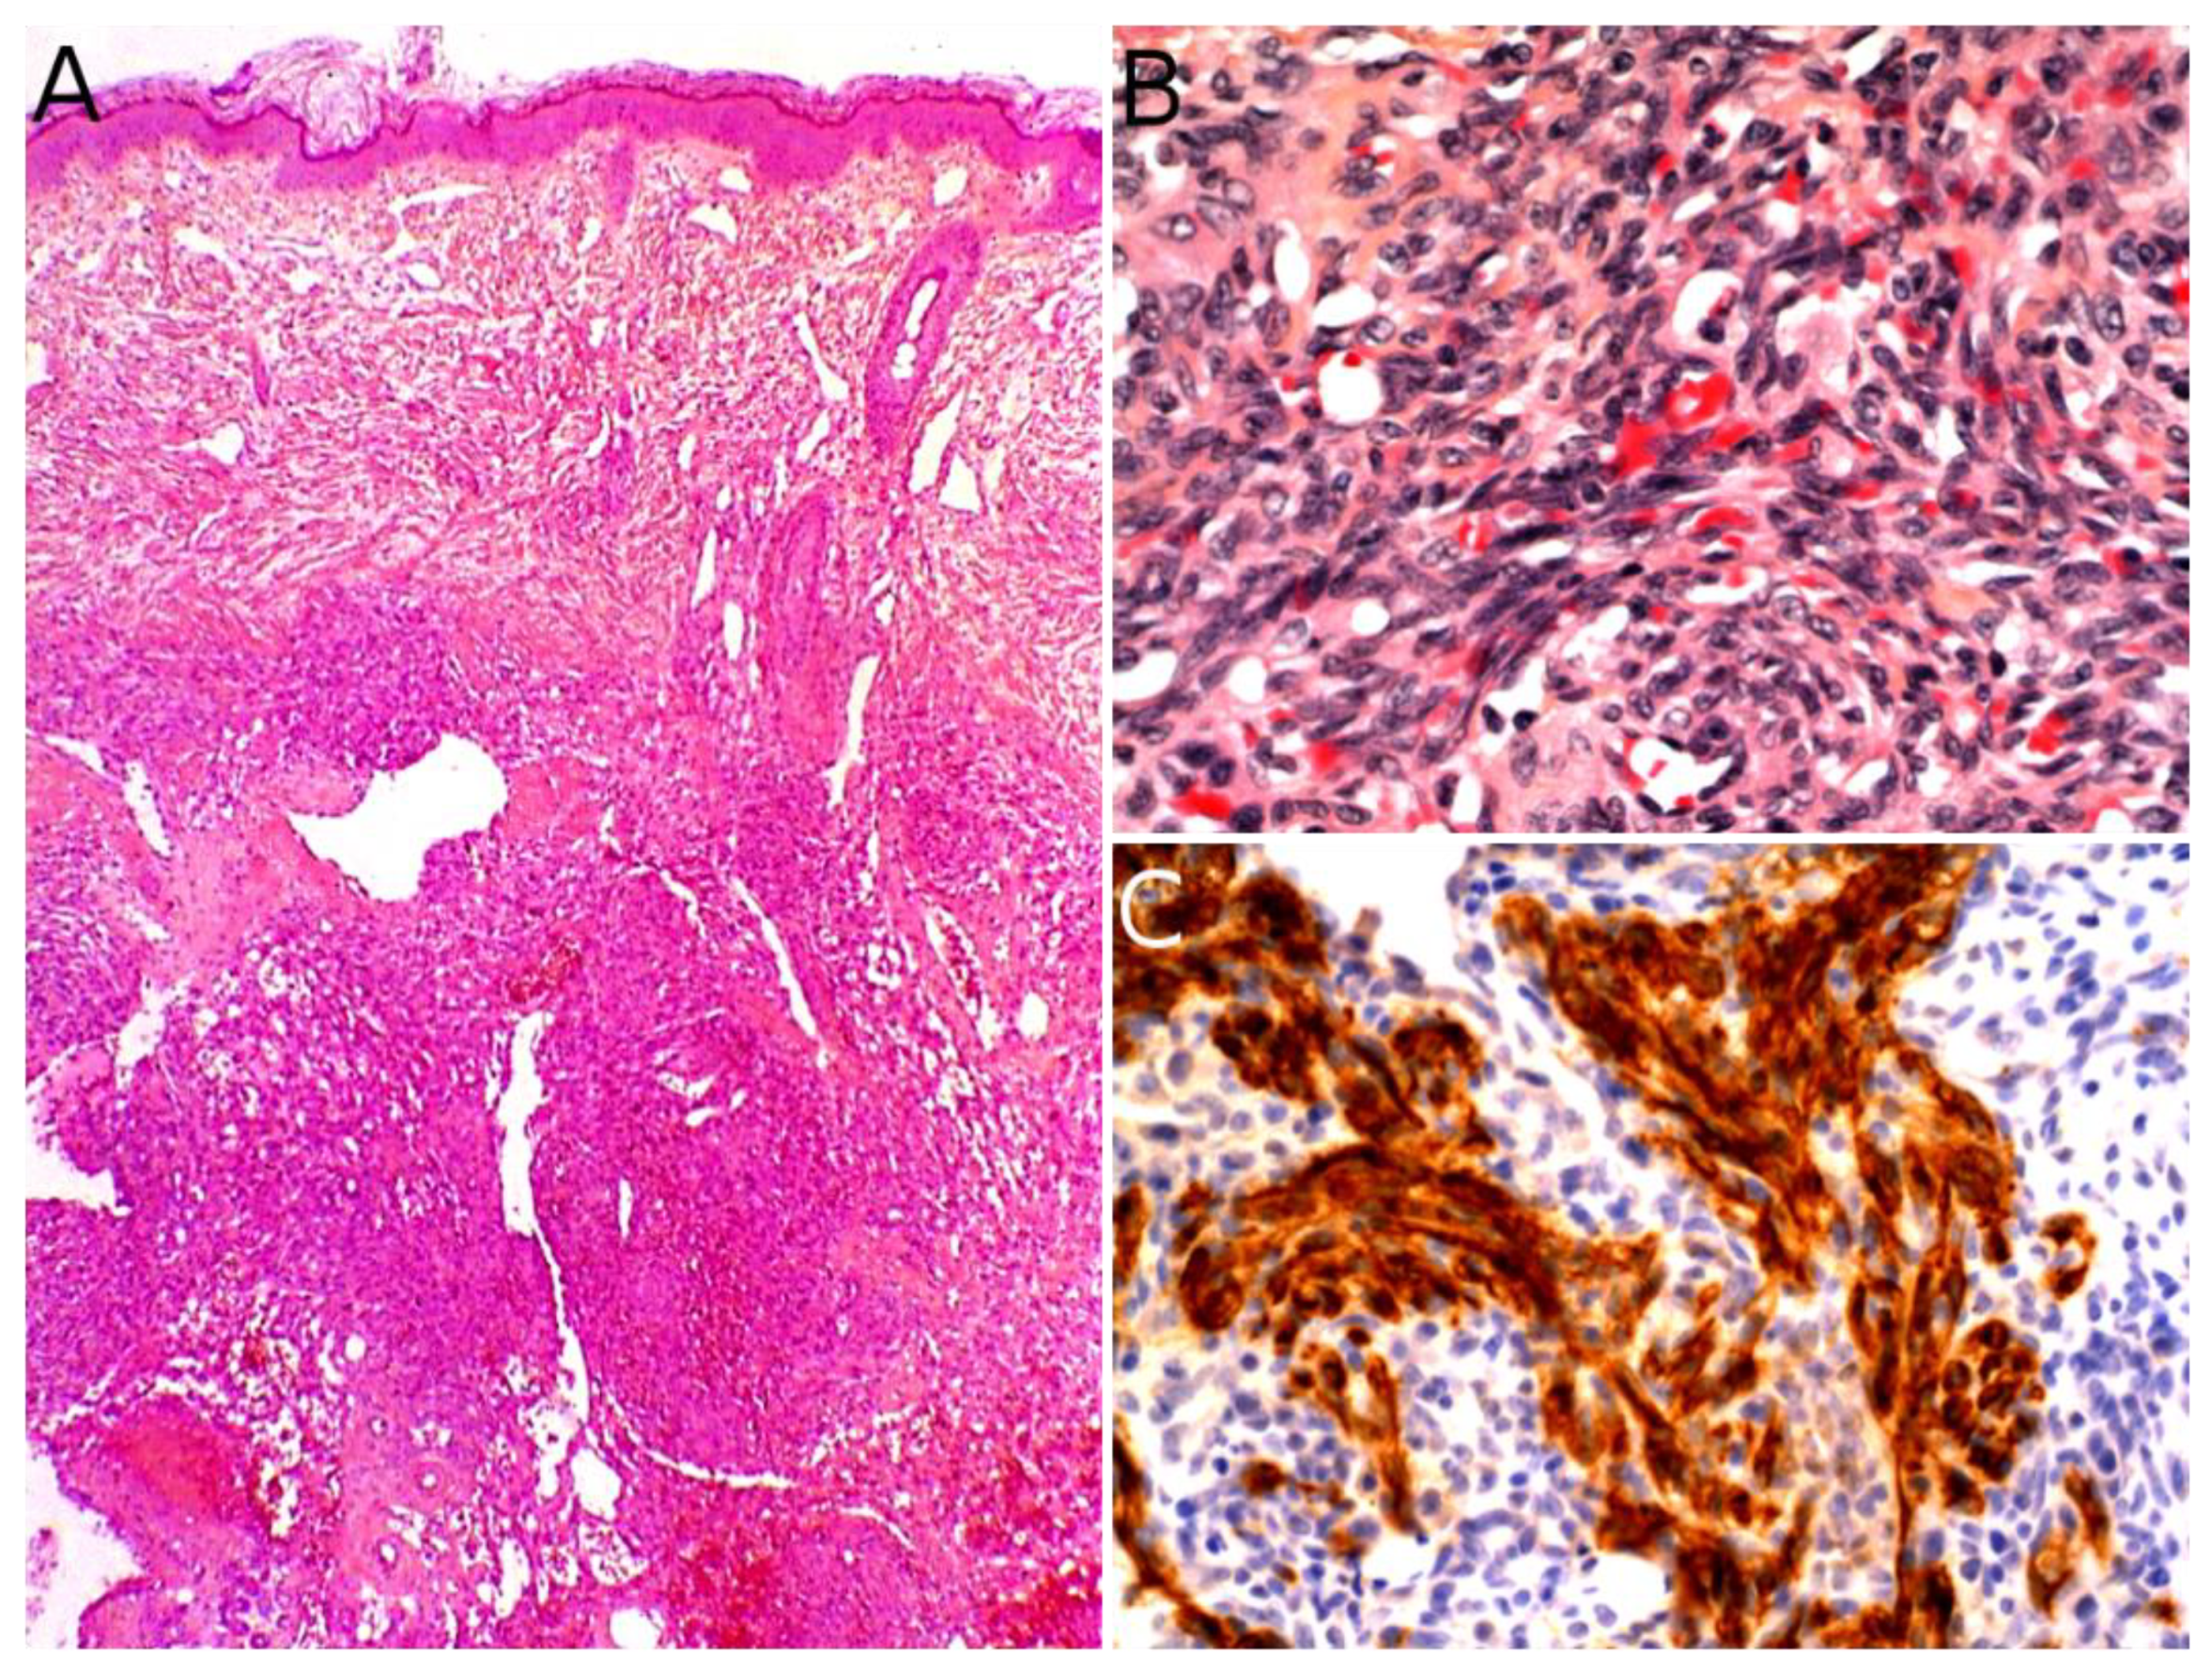

3.3. Pseudomyogenic Haemangioendothelioma

3.4. Angiosarcoma